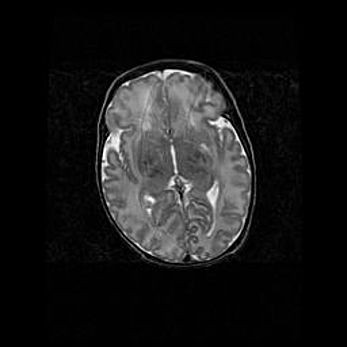

Аномалия Денди-Уокера. Признаки гипоплазии мозолистого тела.

Возраст: 5 месяцев 3 дня

Вес: 5550 г

Пол: мужской

Окружность головы: 39 см

Срок гестации: 40 недель

Аномалия Денди-Уокера – это порок развития головного мозга, для которого характерна триада симптомов: гипотрофия или аплазия червя мозжечка и/или полушарий мозжечка, расширение четвёртого желудочка с формированием ликворной кисты задней черепной ямки, гипертензионная гидроцефалия различной степени.

Гипоплазия мозолистого тела относится к дефектам внутриутробного этапа развития мозговой ткани, возникающим в процессе закладки структур головного мозга, что происходит на начальных этапах развития эмбриона.